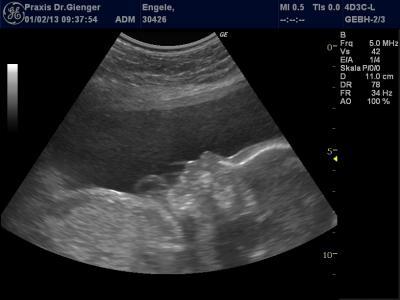

Ich hatte neben dem Zuckerbelastungstest auch noch die monatl. VU. Beim Baby ist alles so wies sein soll. der Arzt prüft auch seit anfang der ss jedesmal die Plazentadurchblutung auf beiden Seiten, und NSdurchblutung-also alles i.O. Nur wegen meiner Übelkeit mag er jetzt doch nen Gastroenterologen zu Rate ziehen ...soll mir umgehend einen Termin machen. Erst war er ewig entspannt und heute hat er dahingehend ne Welle gemacht. Naja hab heut keinen mehr erreicht, da wir noch beim Kiarzt waren danach, dann kurz in der Stadt was Essen, und beim H&M u C&A Babysachen schauen, aber mit hat nix gefallen dort. Das kleine Mädchen ( er hat gesagt wenn es rauskommt und keins sein sollte, darf ichs bei ihm abgeben ) wiegt jetzt 721g und ist 31 cm lang. Super Durchscnitt, Werte entsprechen meiner Woche meinte der Computer bin jetzt in der 25.ssw. Ach ja, unsem Hund geht es grad schon wieder nicht so doll-echt doof, der muss zum Tierarzt, ist jetzt aber auch net so doll heut abend mehr. Hier noch ein Seitenprofilbild Mausi war sehr aktiv, alle 3d Bilder waren die Hände unterschiedlich vorm Gesicht, deswegen heute nur so

Bild zu Heute Vu und Foto - Forum für Mai - Mamis